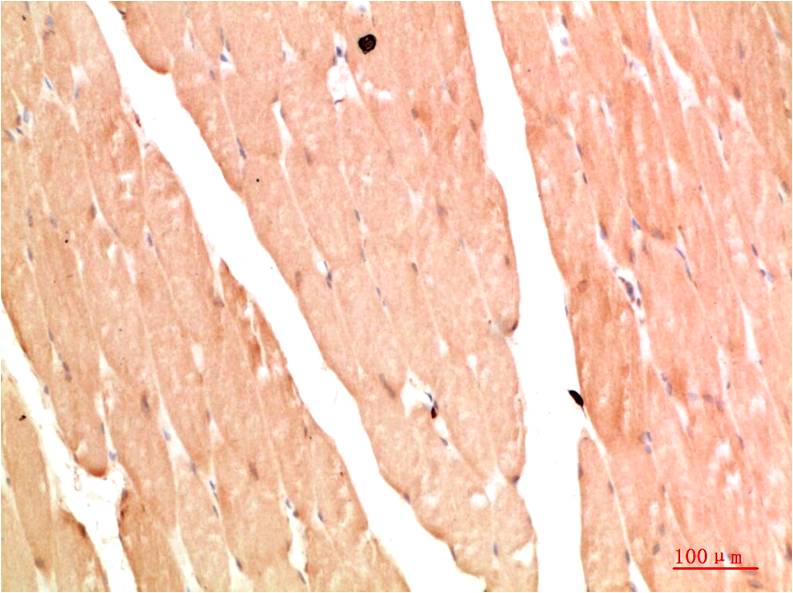

STAT1 Rabbit Polyclonal Antibody

Applications :WB, IHC

| Recommended dilutions: | WB:1:1,000-2,000 IHC:1:200-500 |